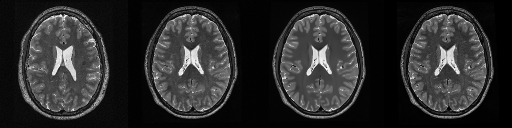

HCP T2w dataset

We utilize images from the publicly available Human Connectome Project (HCP) [51] T2-weighted (T2w) images dataset for the task of compressed sensing, which contains brain images from 47 patients. The HCP dataset includes cross-sectional images of the brain taken at different levels and angles.

Compressed sensing

We train a flow-based model from scratch on 10,000 randomly sampled images, utilizing the ncsnpp architecture [9] with minor adaptations for grayscale images. We employ compression rates , meaning . The measurement operator is given by a subsampled Fourier matrix, whose sign patterns are randomly selected. We evaluate our reconstruction algorithm’s performance on 200 randomly sampled test images.

We present the quantitative and qualitative results of compressed sensing in Tab. 1 and Fig. 4, respectively. As shown in Tab. 1, our method consistently achieves the best performance across varying compression rates . In Fig. 4, our method produces reconstructions that are more faithful to the original images, with fewer artifacts, leading to higher accuracy and clearer details.